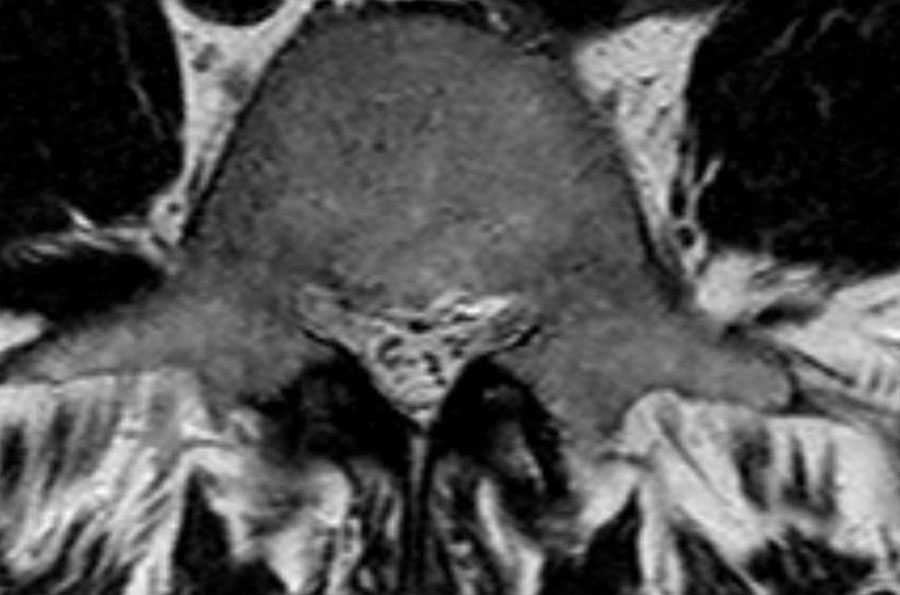

Cuộn qua các hình ảnh để quan sát đường đi của các rễ thần kinh tại mức độ đĩa đệm, ngách bên, lỗ liên hợp và ngoài lỗ liên hợp.

Tại mỗi mức độ có thể thấy các bệnh lý đặc trưng, nhưng có sự chồng lấp đáng kể.

Đây được gọi là thoát vị thực sự (extrusion), vì khoảng cách giữa các bờ của khối thoát vị lớn hơn khoảng cách tại nền. - Rễ thần kinh L5 bị chèn ép (mũi tên xanh dương) trong ngách bên.

Đĩa đệm thoát vị đã di trú xuống phía dưới và được thấy như một cấu trúc hình bầu dục nằm phía trước rễ thần kinh.

Đĩa đệm thoát vị không được bao bọc, tức là không được che phủ bởi các sợi của vòng sợi.